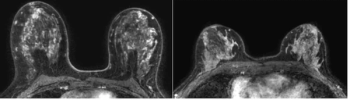

An emerging deep learning algorithm had a lower AUC and sensitivity than urological radiologists for differentiating between small renal masses on computed tomography (CT) scans but had a 21 percent higher sensitivity rate than non-urological radiologists, according to new research.